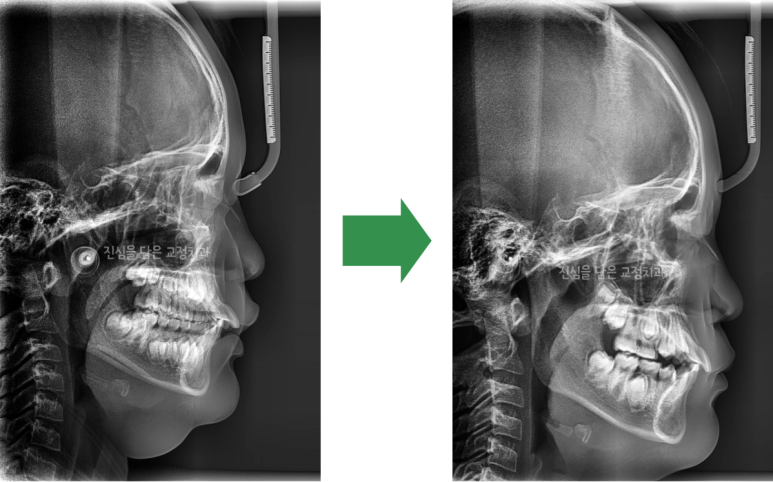

처음 내원하였을 때와 1차 교정 후 옆 얼굴 엑스레이 사진을 비교해보면 아래턱의 위치가 개선된 것을 확인할 수 있습니다. 또한 뻐드러진 위 앞니 각도도 일정부분 개선되었습니다. 트윈블럭 사용 이후의 골격, 얼굴 모습, 교합 관계에 대한 정확한 분석을 통해 2차 교정 시 발치 여부를 결정하게 됩니다.